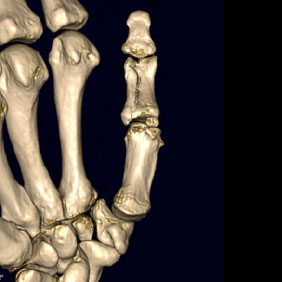

Tomografía computarizada Osteoarticular

< Volver a "Tomografía Computarizada (TC) con Inteligencia artificial"Con esta prueba valoraremos la patología de las vertebras, fracturas, hernias, protusiones discales, …